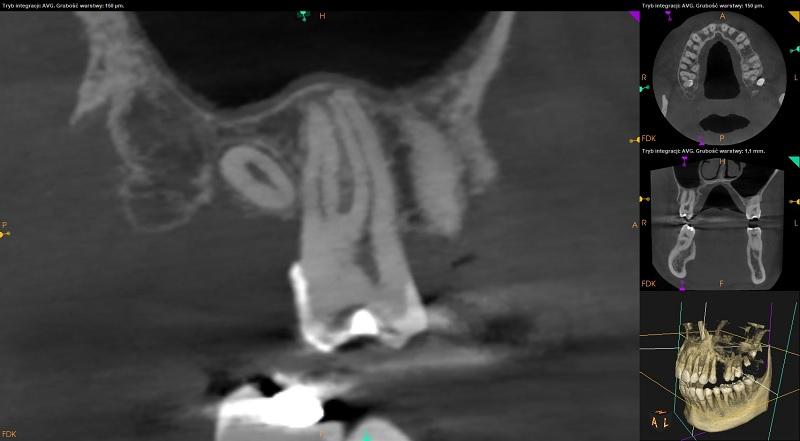

Szczęka.

Zatoki szczękowe powietrzne.

Przyścienne pogrubienie błony śluzowej w zachyłkach zębodołowych po stronie prawej i lewej (do 3mm).

Ciągłość blaszki kortykalnej dna zatok szczękowych przerwana w okolicy wierzchołków korzeni zębów 17,16 po stronie prawej, 26,27,28 i 29 po stronie lewej.

Widoczny uogólniony zanik wysokości tkanki kostnej wyrostka zębodołowego szczęki (ubytek kości około 3,5mm) oraz ścieńczenie blaszki zbitej po stronie przedsionkowej przy zębach 14,22,24.

Ząb 18 – mikrodontyczny. Zatrzymany, położony poziomo. Koroną skierowany w stronę podniebienną.

Ząb 17 - bez znamion leczenia kanałowego. Widoczne cztery światła kanałów. Szpara ozębnej wokół wierzchołka korzenia podniebiennego poszerzona.

Pozostałe zęby bez znamion leczenia kanałowego. Tkanki okołowierzchołkowe bez widocznych radiologicznie cech patologicznych.

Ząb 28 – mikrodontyczny. Położony pionowo. Wierzchołek korzenia przerywa ciągłość blaszki kortykalnej dna zatoki szczekowej lewej.

Ząb 29 – mikrodontyczny. Położony po stronie policzkowej wyrostka, pionowo skośnie. Koroną skierowany w stronę mezialną. Ząb przerywa ciągłość blaszki kortykalnej dna zatoki szczekowej lewej oraz blaszki zbitej po stronie policzkowej.

Radiologiczne przejaśnienia mogące odpowiadać próchnicy lub ubytkom w zębach: 16 – strona mezialna poniżej wypełnienia, 22 – strona mezialna - do dalszej diagnostyki klinicznej.

Pozostałe zęby bez znamion leczenia kanałowego. Tkanki okołowierzchołkowe bez widocznych radiologicznie cech patologicznych. Ząb 28 – mikrodontyczny. Położony pionowo. Wierzchołek korzenia przerywa ciągłość blaszki kortykalnej dna zatoki szczekowej lewej.